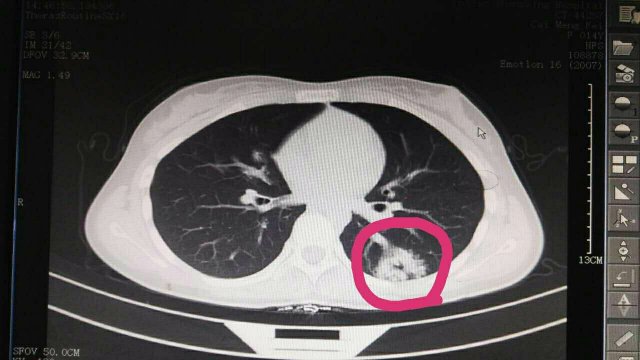

蔡**,女,14歲因“反覆頭暈3年余”,求診莆田及莆田各三級醫院,做過(guò)很多輔助檢查,均未確診,于2017-2-26日就診我院門(mén)診,接診是我院兒科林富醫師,經(jīng)過(guò)認真仔細查體,發(fā)現患兒左側肩胛骨可聞及Ⅱ-Ⅲ/Ⅵ級收縮期雜音,為明確診斷,即刻請我院莊姞副主任醫師(原莆田市Di一醫院NICU主任)會(huì )診,查胸部CT發(fā)現左肺下葉背段血管畸形。莊姞副主任醫師告訴我們,部分型肺血管畸形如果不認真查體是很難查體的到,年輕醫師能如此仔細查體,確診多家醫院未確診的疾病,不得不對林醫生豎起大拇指,通過(guò)此次經(jīng)歷,可見(jiàn)臨床醫生必須熟練掌握臨床三基的重要性。